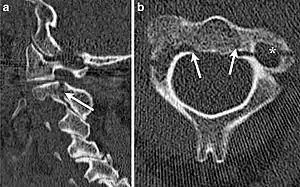

Hangman's fracture is the colloquial name given to a fracture of both pedicles, or partes interarticulares, of the axis vertebra (C2).[1]

Although a hangman's fracture is unstable, survival from this fracture is relatively common, as the fracture itself tends to expand the spinal canal at the C2 level. It is not unusual for patients to walk in for treatment and have such a fracture discovered on X-rays. Only if the force of the injury is severe enough that the vertebral body of C2 is severely subluxed from C3 does the spinal cord become crushed, usually between the vertebral body of C3 and the posterior elements of C1 and C2.